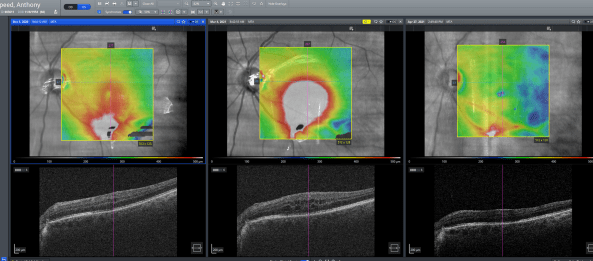

Where am I now? A little over a month ago at the end of March, I underwent a third operation, this time to remove the oil in my eye and replace it with gas again. This had always been planned, but became more urgent due to the oil causing my retina to become inflamed. We had tried steroid drops to control and reduce the inflammation a month prior but as the photo below shows this was not successful, so back under the knife again.